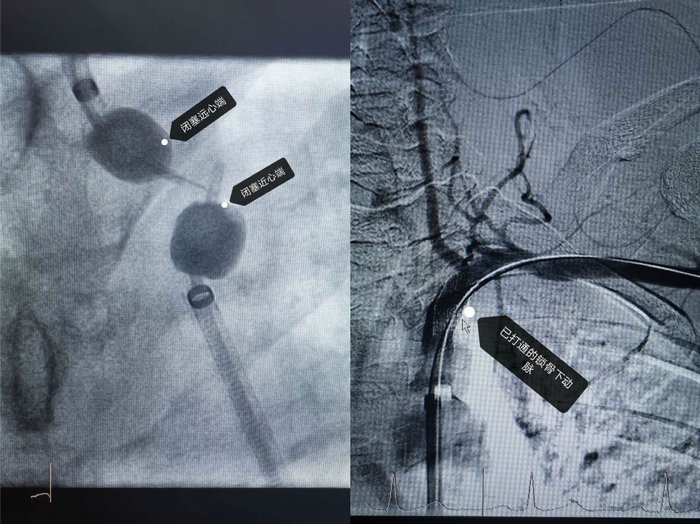

完善一系列的术前准备后,4月20日下午,沈利明为陆先生实施了微创手术治疗,术中造影发现陆先生左侧锁骨下动脉完全闭塞,闭塞长度达10mm,再次开通难度非常之大。好在沈利明术前已充分考虑到手术的难度,特地准备的一些“非常规*器武**”纷纷被用上场,最终还是有惊无险的开通了完全闭塞的左侧锁骨下动脉,最后的造影显示左侧锁骨下动脉血流通畅,通往大脑的颈动脉和椎动脉血流也没有收到影响。术后第二天,陆先生双上肢的血压几乎一致了,左手麻木的症状也消失了。术后第三天,陆先生就康复出院了,手术效果立竿见影,陆先生为此非常感激。